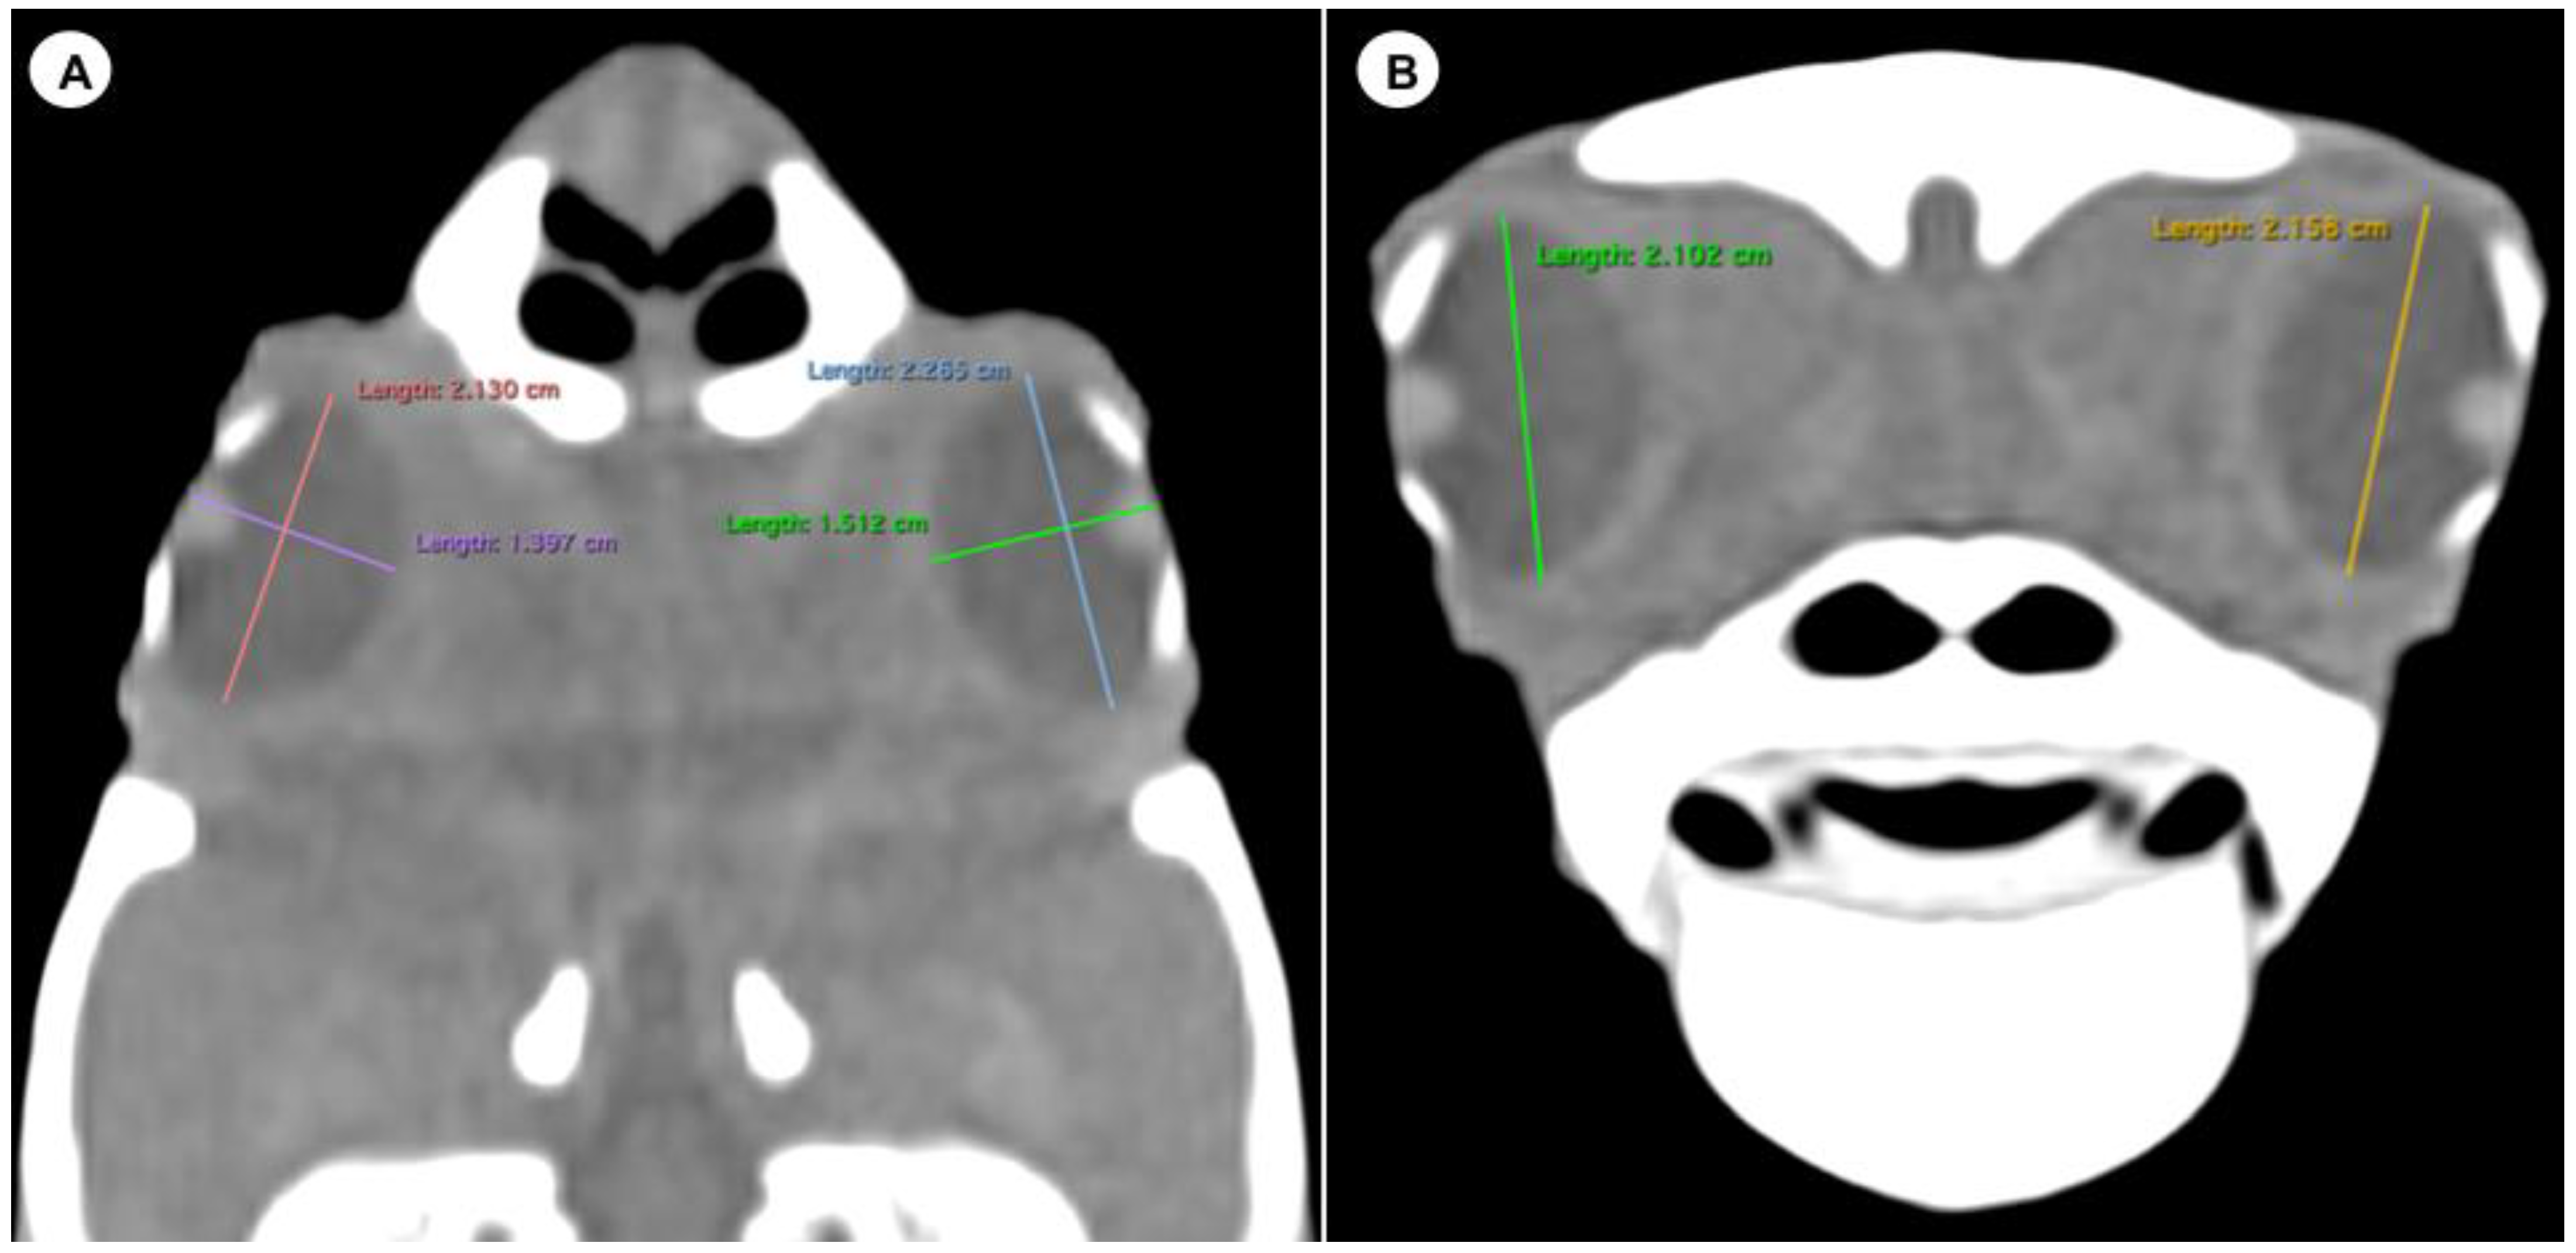

- (B)

- Transverse plane concerning the turtle’s body

- Dorsal and ventral arch length: the thickness of the upper and lower regions of the scleral ring, with the corneal and scleral margins (Figure 2B).

- Width of the dorsal and ventral arches of the scleral ring, that is, of the upper and lower parts of the lateral portion of the ring (Figure 2A).